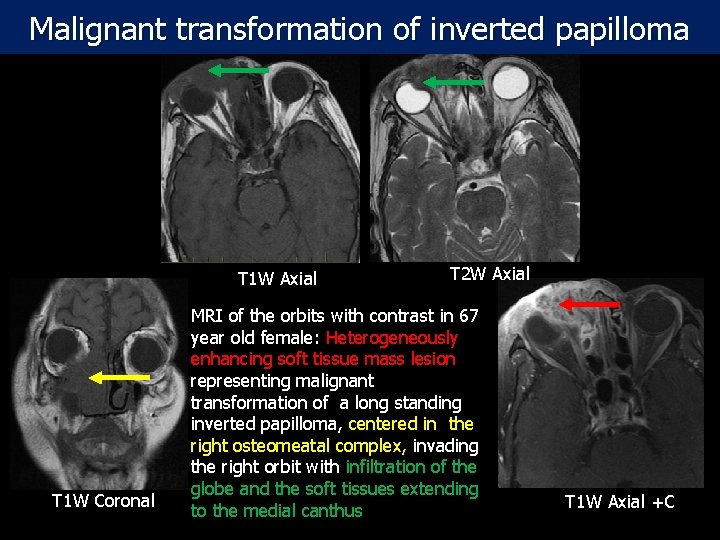

Malignant transformation of inverted papilloma T 1 W Axial T 1 W Coronal T 2 W Axial MRI of the orbits with contrast in 67 year old female: Heterogeneously enhancing soft tissue mass lesion representing malignant transformation of a long standing inverted papilloma, centered in the right osteomeatal complex, invading the right orbit with infiltration of the globe and the soft tissues extending to the medial canthus T 1 W Axial +C